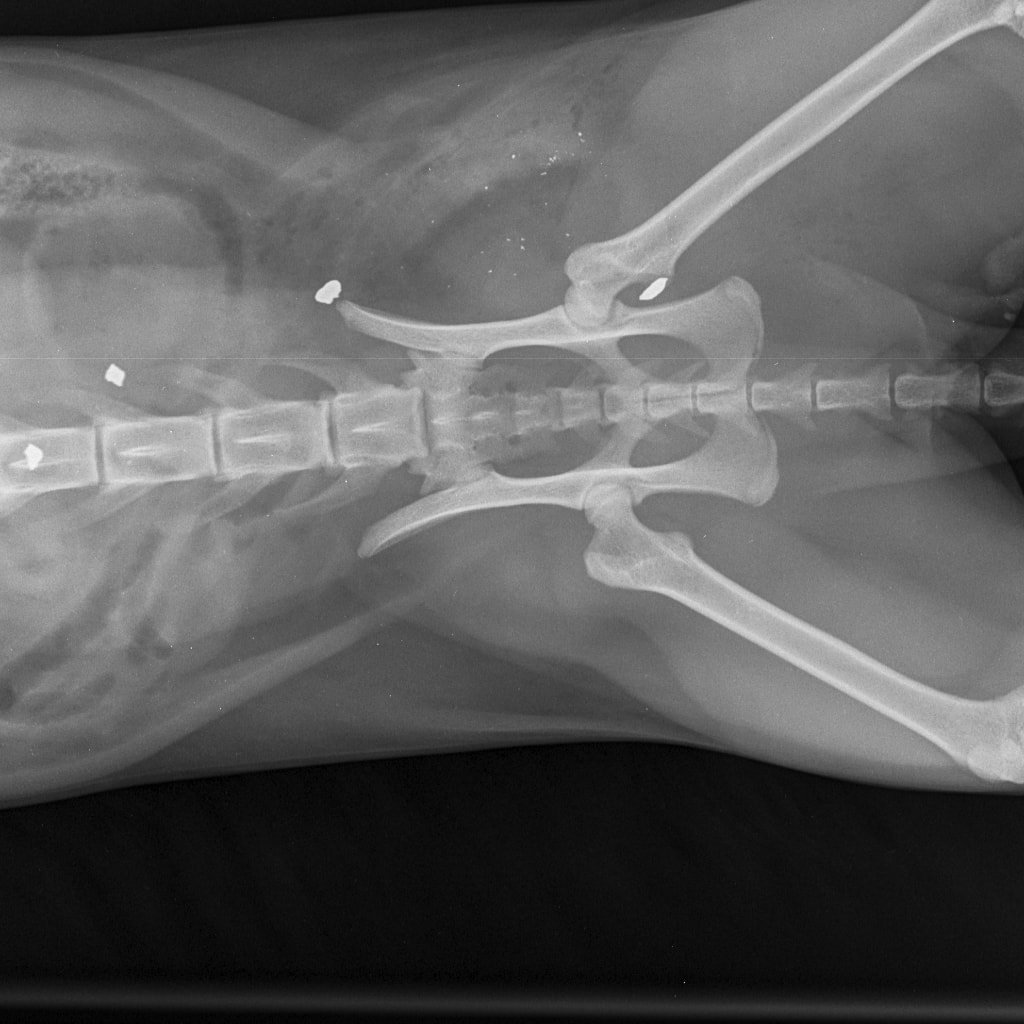

– Nikako ne mogu razumjeti da mi je netko namjerno ubio životinju. I to metkom koji se rasprsnuo u tijelu malene životinje što nije metak iz zračne puške. To se lijepo i vidi na rendgenskoj snimci koju smo obavili u Veterinarskoj ambulanti Majcan. U svakom slučaju, prijavili smo sve policiji koja će, iskreno se nadam, čim prije pronaći krivca – rekla nam je tužna vlasnica ubijene životinje.